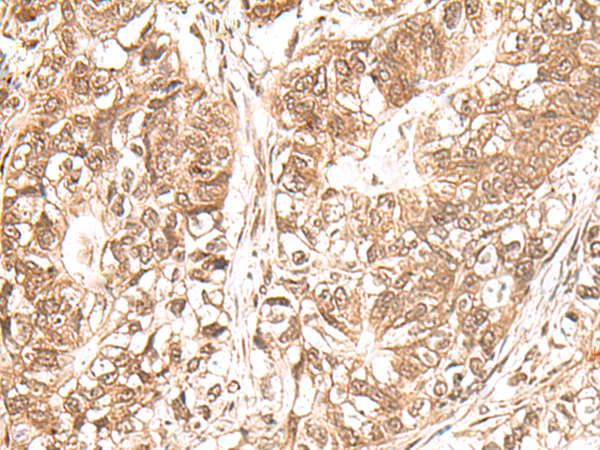

IHC positive control:

Human gastric cancer and Human ovarian cancer